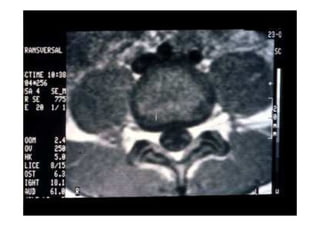

• Cifose pós-traumática

• Resumo do caso: Queda da própria altura com diminuição de força de

membros inferiores de forma gradativa.

• Paciente (dados): Sexo feminino, 54 anos

• História: Queda da própria altura durante internação hospitalar em outro

serviço para tratamento de crise de ativação do LES há 6 meses. Apresentou

diminuição de força de membros inferiores de forma gradativa. Foi avaliada

no serviço de origem e realizado TC e aventada a hipótese de mielite

transversa. Foi encaminhada ao CRER para reabilitação. Nesse momento

apresentava apenas parestesia em MMII e FM grau 0 (ASIA B).

• Diagnóstico(s): Consolidação viciosa de T5, com cifose pós-traumática e

compressão medular (ASIA B)

• Antecedentes de Lúpus (LES), uso crônico de corticóide e tabagismo severo

• Tratamento(s): Realizada vertebrectomia com descompressão medular e

reconstrução com Mesh CAGE e artrodese de T2 a T8 por via posterior.

• Seguimento ("Follow up"): PO 1 ano com boa melhora funcional da

paciente.

• Resultado Final: Paciente apresentou melhora gradativa da força muscular e

da função, estando hoje com força muscular grau IV em MMII, conseguindo

deambular e inclusive subir e descer escadas com apoio (ASIA D).

Fonte: Portal da SBC – casos clínicos

RM - corte axial imagem ponderada em T2